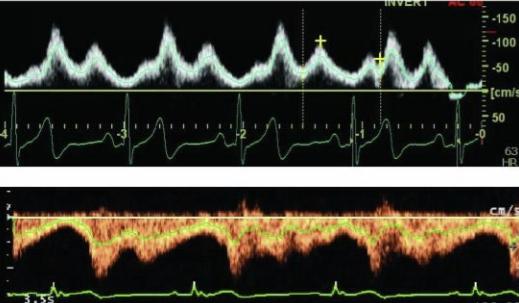

A duplex scan is a vascular ultrasound that examines the characteristics (such as speed and direction) of blood flow in a vein and/or artery. It merges real-time imaging (2D B-mode ultrasound) with two modes of Doppler ultrasound: spectral Doppler and color Doppler. Color Doppler produces a color image of the vessel overlaid on a B-mode ultrasound image, showing both structure and blood flow velocity and direction

Spectral Doppler presents a graphic display of Doppler data, with jagged vertical lines called waveforms representing flow velocity The vertical axis shows flow velocity in centimeters per second. Higher spikes represent more rapid within blood flow in the vessel. Spectral and color Doppler must both be performed and documented to substantiate a duplex code.

Per the CPT® manual, a duplex scan requires ?real-time images integrating B-mode two dimensional vascular structure, Doppler spectral analysis, and color flow Doppler imaging.? Per Clinical Examplesin Radiology(Winter 2015), when color Doppler is performed alone (without spectral Doppler) to visualize anatomic structures with concurrent real-time ultrasound, it is included in the non-vascular ultrasound code